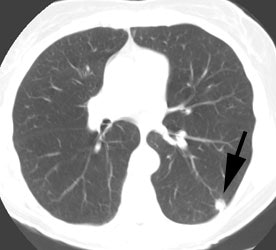

Unsuspected bone metastases: The patient shown below had a cavitary left lung non-small cell lung cancer. There was no uptake of tracer within the aortopulmonary window lymph nodes detected on CT to suggest metastases, however, unsuspected bone metastases were found in the left anterior 4th rib (black arrow) and lumbar spine (red arrows- not included in staging lung CT scan). The presence of bone metastases significantly alters patient prognosis and management. PET imaging provides a rapid whole body survey for the detection of unsuspected metastatic disease. |

|